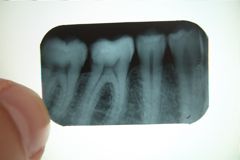

Wortelkanaal

Kies

Ik ben ontzenuwd. Na een niet al te geslaagde vulling in december had ik al vaker last van m’n eerste molaar (46), maar m’n tandarts vond dat er niets aan de hand was. Gisteravond was het niet meer leuk. Ik kon vanmiddag meteen naar de waarnemend arts, die meteen maar eens een wortelkanaalbehandeling is begonnen. Dat deed gelukkig niet zeer (dat zal te maken hebben met de vijf verdovingen). En met een tabletje ibuprofen is er nu (nog) niks aan de hand. Volgende week wordt de klus afgemaakt, en daarna ga ik nooit meer naar de tandarts. Zie rechts mijn kies voor de behandeling.